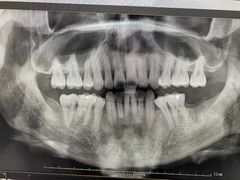

想养一只格洛米 | 22-02-22

报错

• -牙博士口腔品牌连锁(杨浦店)